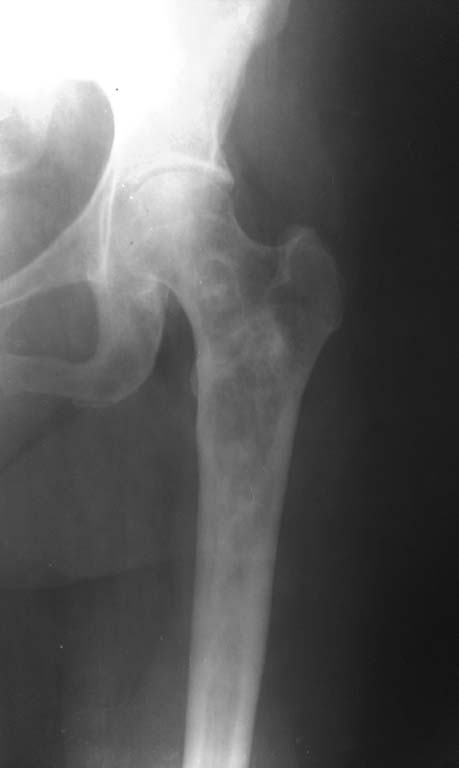

Пациентка 1952 г.р.  (61 лет), поступила жалобами: на непостоянные боли

в области левого тазобедренного сустава, верхней трети бедра и суставов

конечностей.

Anamnesis morbi: Со слов пациентки болеет в течении 2,5лет, когда

появились боли в бедре и крупных суставах. Об-но: по внутренним органам

без особенностей. Пальпаторно отмечается болезненность в проекции

верхней–  средней трети левой бедренной кости.

04.09.13г 1-м этапом произведена: Операционная биопсия из проксимального

отдела левой бедренной кости. Заключение патолого - гистологического

исследования: Дегенеративное поражение костной ткани с замещением

незрелой фиброзной тканью. В анализах в пределах нормы.

Резекцию проксимального отдела левой бедренной кости. Тотальное

цементное эндопротезирование левого тазобедренного сустава модульным

имплантом.